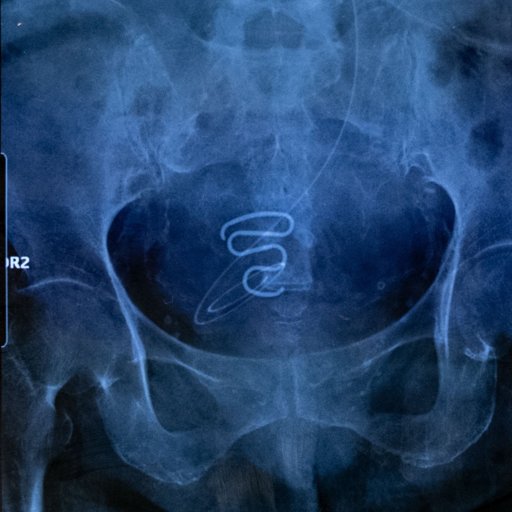

Entre 1966 et 1975, des milliers d’Inuites – souvent mineures – se sont vu poser de force un stérilet. La photographe Juliette Pavy a recueilli le récit de ces femmes victimes d’une campagne de dépeuplement menée par l’État danois, qui leur présente aujourd’hui ses excuses. The post Contraceptions forcées au Groenland : la fin d’un secret appeared first on Revue21.fr.